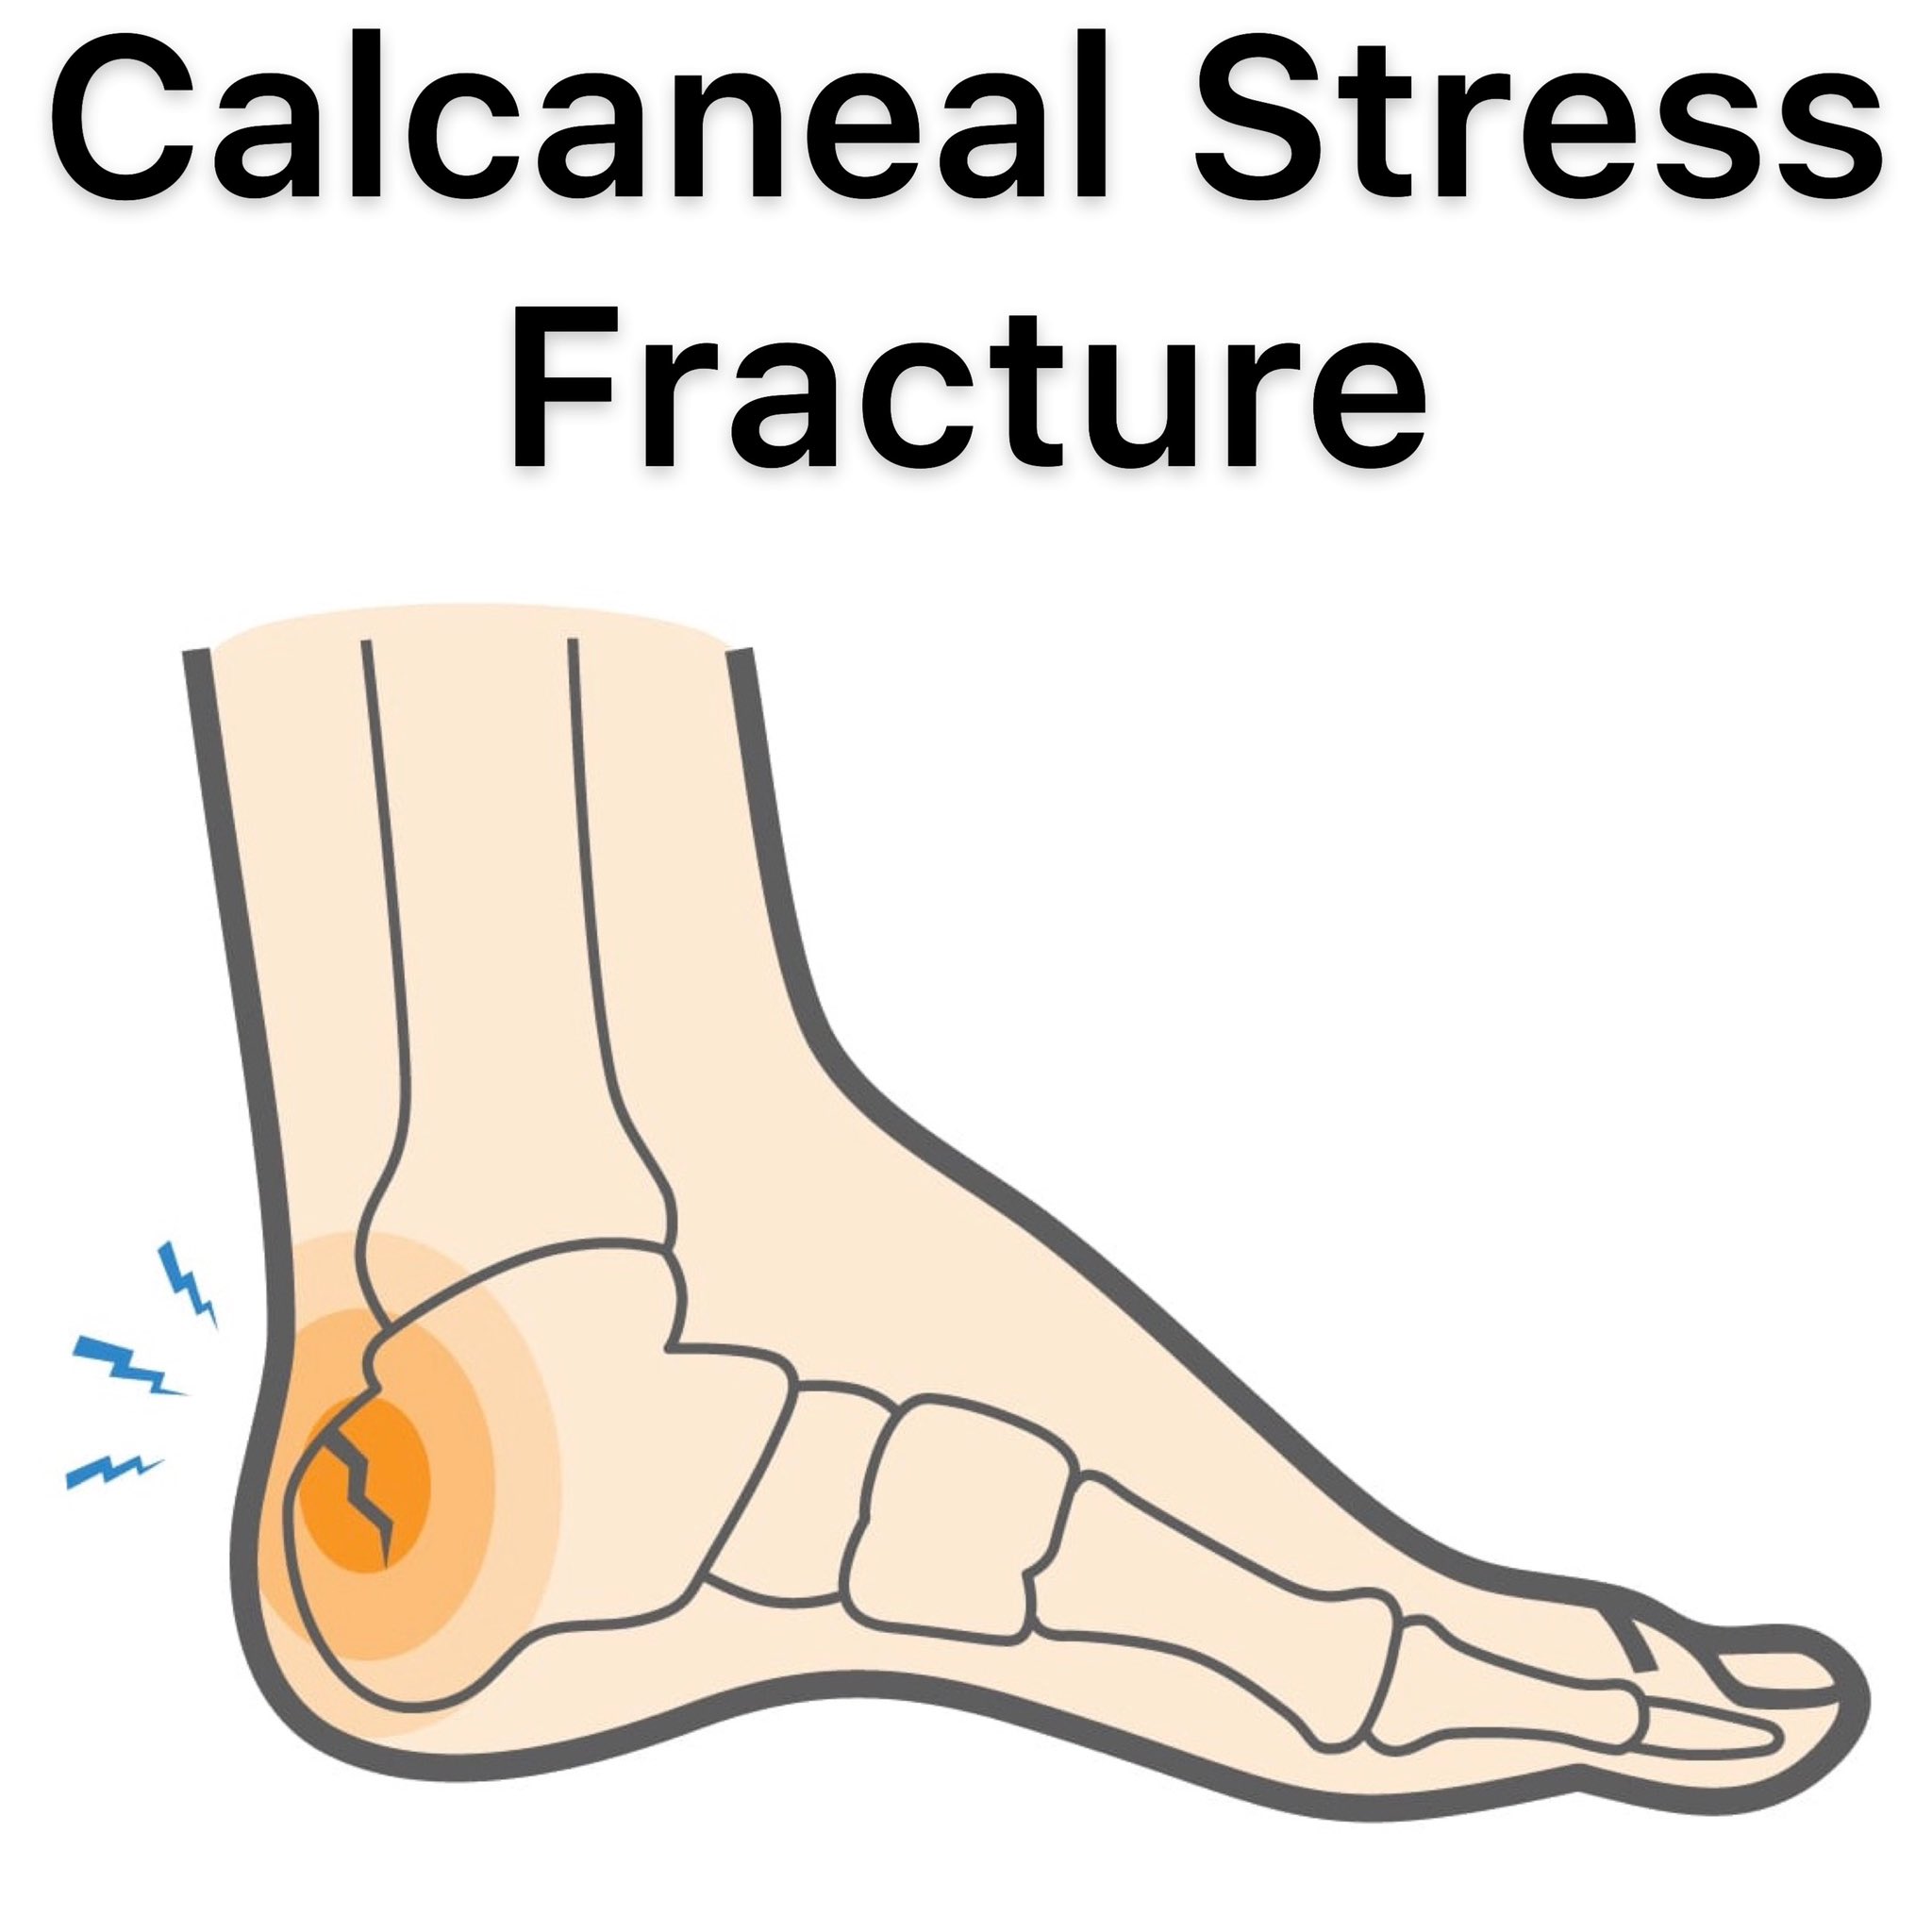

Fracture of the Heel Bone Calcaneus Orthoriverside outlet, Heal Bone Fractures Calcaneal Fractures outlet, Fractures of the Heel Bone Injuries and Poisoning Merck outlet, What is a Calcaneal Stress Fracture How to Recover Upswing Health outlet, Calcaneus Fracture Broken Heel Bone Orthopaedic Trauma outlet, Calcaneus Fracture Broken Heel Bone Orthopaedic Trauma outlet, Calcaneus Heel Bone Fractures OrthoInfo AAOS outlet, Calcaneal Fracture Broken Heel Bone Plantar Fasciitis outlet, Did I Break My Heel Bone Dr. Elton outlet, Calcaneal Fracture Treatment Exercises FAQs Case outlet, Calcaneal Fractures Physiopedia outlet, Fractures of the Heel UConn Musculoskeletal Institute outlet, Calcaneus Fracture Broken Heel Bone Campbell Clinic Orthopaedics outlet, Calcaneal fracture Wikipedia outlet, Heel Bone Calcaneus Fractures Newport Orthopedic Institute outlet, Calcaneus Fracture Broken Heel Bone Orthopaedic Trauma outlet, Calcaneus Fracture Broken Heel Bone Campbell Clinic Orthopaedics outlet, Calcaneal Fracture Symptoms Causes Treatment and Rehabilitation outlet, Calcaneus Heel Bone Fractures OrthoInfo AAOS outlet, Treating Fracture of the Heel Bone in Plano Frisco McKinney and outlet, Did I Bruise Or Fracture My Heel The Orthopaedic Foot Ankle outlet, Calcaneus Fracture Broken Heel Bone We treat this injury outlet, Calcaneus Fracture Broken Heel Bone Orthopaedic Trauma outlet, Calcaneus Fracture A Broken Heel Bone outlet, Understanding Calcaneus Heel Fracture Repair Saint Luke s outlet, Broken Foot Fractured Foot Symptoms Treatment Recovery outlet, Heel Bone Fracture Treatment Options OrthoIndy Blog outlet, A Calcaneal Stress Fracture Means a Broken Heel Bone outlet, Heel Fracture Rehab My Patient outlet, Calcaneus Heel Bone Fractures OrthoInfo AAOS outlet, Fractures of the Calcaneus Heel Bone YouTube outlet, Heel Bone Fracture The Foot Clinic Blog Perth Cottesloe outlet, Top Heel Fracture Treatment in Cincinnati Family Foot Ankle outlet, Broken Heel Calcaneus Fracture Triad Foot and Ankle Center outlet, Calcaneal fracture Wikipedia outlet, Calcaneus Fracture Broken Heel Bone Orthopaedic Trauma outlet, Blog footsurgeon outlet, Walking on Broken Heel Bone Tips for Good Recovery outlet, How Do Heel Spurs Develop InStride Queen City Foot and Ankle outlet, 7 Heel Spur Myths and Facts Heel That Pain outlet, Calcaneus Heel Bone Fracture Best Foot Surgeon Los Angeles UFAI outlet, Calcaneus Fracture Surgery Heel Surgery FootCareMD outlet, Heel Bone Calcaneal Fracture DOC outlet, KAATSU Global Blog Crack In The Calcaneus Healing With KAATSU outlet, Fracture of the Heel Bone Calcaneus Willis Knighton Health System outlet, Haglund s Deformity Causes Treatment My FootDr outlet, Heel Pain Causes Symptoms Diagnosis Prevention and Treatments outlet, Bruised Heel Heel Pain Treatment Melbourne Podiatrist outlet, Heel Spurs How to Manage Them Dr. Scholl s outlet, Sports Physiotheray on X outlet.

Fracture of the Heel Bone Calcaneus Orthoriverside outlet, Heal Bone Fractures Calcaneal Fractures outlet, Fractures of the Heel Bone Injuries and Poisoning Merck outlet, What is a Calcaneal Stress Fracture How to Recover Upswing Health outlet, Calcaneus Fracture Broken Heel Bone Orthopaedic Trauma outlet, Calcaneus Fracture Broken Heel Bone Orthopaedic Trauma outlet, Calcaneus Heel Bone Fractures OrthoInfo AAOS outlet, Calcaneal Fracture Broken Heel Bone Plantar Fasciitis outlet, Did I Break My Heel Bone Dr. Elton outlet, Calcaneal Fracture Treatment Exercises FAQs Case outlet, Calcaneal Fractures Physiopedia outlet, Fractures of the Heel UConn Musculoskeletal Institute outlet, Calcaneus Fracture Broken Heel Bone Campbell Clinic Orthopaedics outlet, Calcaneal fracture Wikipedia outlet, Heel Bone Calcaneus Fractures Newport Orthopedic Institute outlet, Calcaneus Fracture Broken Heel Bone Orthopaedic Trauma outlet, Calcaneus Fracture Broken Heel Bone Campbell Clinic Orthopaedics outlet, Calcaneal Fracture Symptoms Causes Treatment and Rehabilitation outlet, Calcaneus Heel Bone Fractures OrthoInfo AAOS outlet, Treating Fracture of the Heel Bone in Plano Frisco McKinney and outlet, Did I Bruise Or Fracture My Heel The Orthopaedic Foot Ankle outlet, Calcaneus Fracture Broken Heel Bone We treat this injury outlet, Calcaneus Fracture Broken Heel Bone Orthopaedic Trauma outlet, Calcaneus Fracture A Broken Heel Bone outlet, Understanding Calcaneus Heel Fracture Repair Saint Luke s outlet, Broken Foot Fractured Foot Symptoms Treatment Recovery outlet, Heel Bone Fracture Treatment Options OrthoIndy Blog outlet, A Calcaneal Stress Fracture Means a Broken Heel Bone outlet, Heel Fracture Rehab My Patient outlet, Calcaneus Heel Bone Fractures OrthoInfo AAOS outlet, Fractures of the Calcaneus Heel Bone YouTube outlet, Heel Bone Fracture The Foot Clinic Blog Perth Cottesloe outlet, Top Heel Fracture Treatment in Cincinnati Family Foot Ankle outlet, Broken Heel Calcaneus Fracture Triad Foot and Ankle Center outlet, Calcaneal fracture Wikipedia outlet, Calcaneus Fracture Broken Heel Bone Orthopaedic Trauma outlet, Blog footsurgeon outlet, Walking on Broken Heel Bone Tips for Good Recovery outlet, How Do Heel Spurs Develop InStride Queen City Foot and Ankle outlet, 7 Heel Spur Myths and Facts Heel That Pain outlet, Calcaneus Heel Bone Fracture Best Foot Surgeon Los Angeles UFAI outlet, Calcaneus Fracture Surgery Heel Surgery FootCareMD outlet, Heel Bone Calcaneal Fracture DOC outlet, KAATSU Global Blog Crack In The Calcaneus Healing With KAATSU outlet, Fracture of the Heel Bone Calcaneus Willis Knighton Health System outlet, Haglund s Deformity Causes Treatment My FootDr outlet, Heel Pain Causes Symptoms Diagnosis Prevention and Treatments outlet, Bruised Heel Heel Pain Treatment Melbourne Podiatrist outlet, Heel Spurs How to Manage Them Dr. Scholl s outlet, Sports Physiotheray on X outlet.